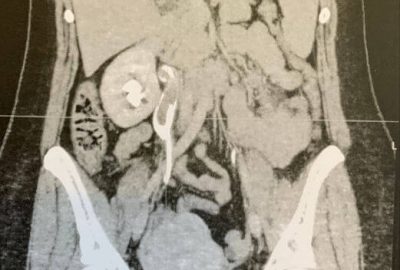

Μετά την κλινική εξέταση ακολούθησε Αξονική τομογραφία η οποία έδειξε λιθίαση του κάτω τριτημορίου (ΑΡ) ουρητήρα με ουρητηρουδρονεφρωση.